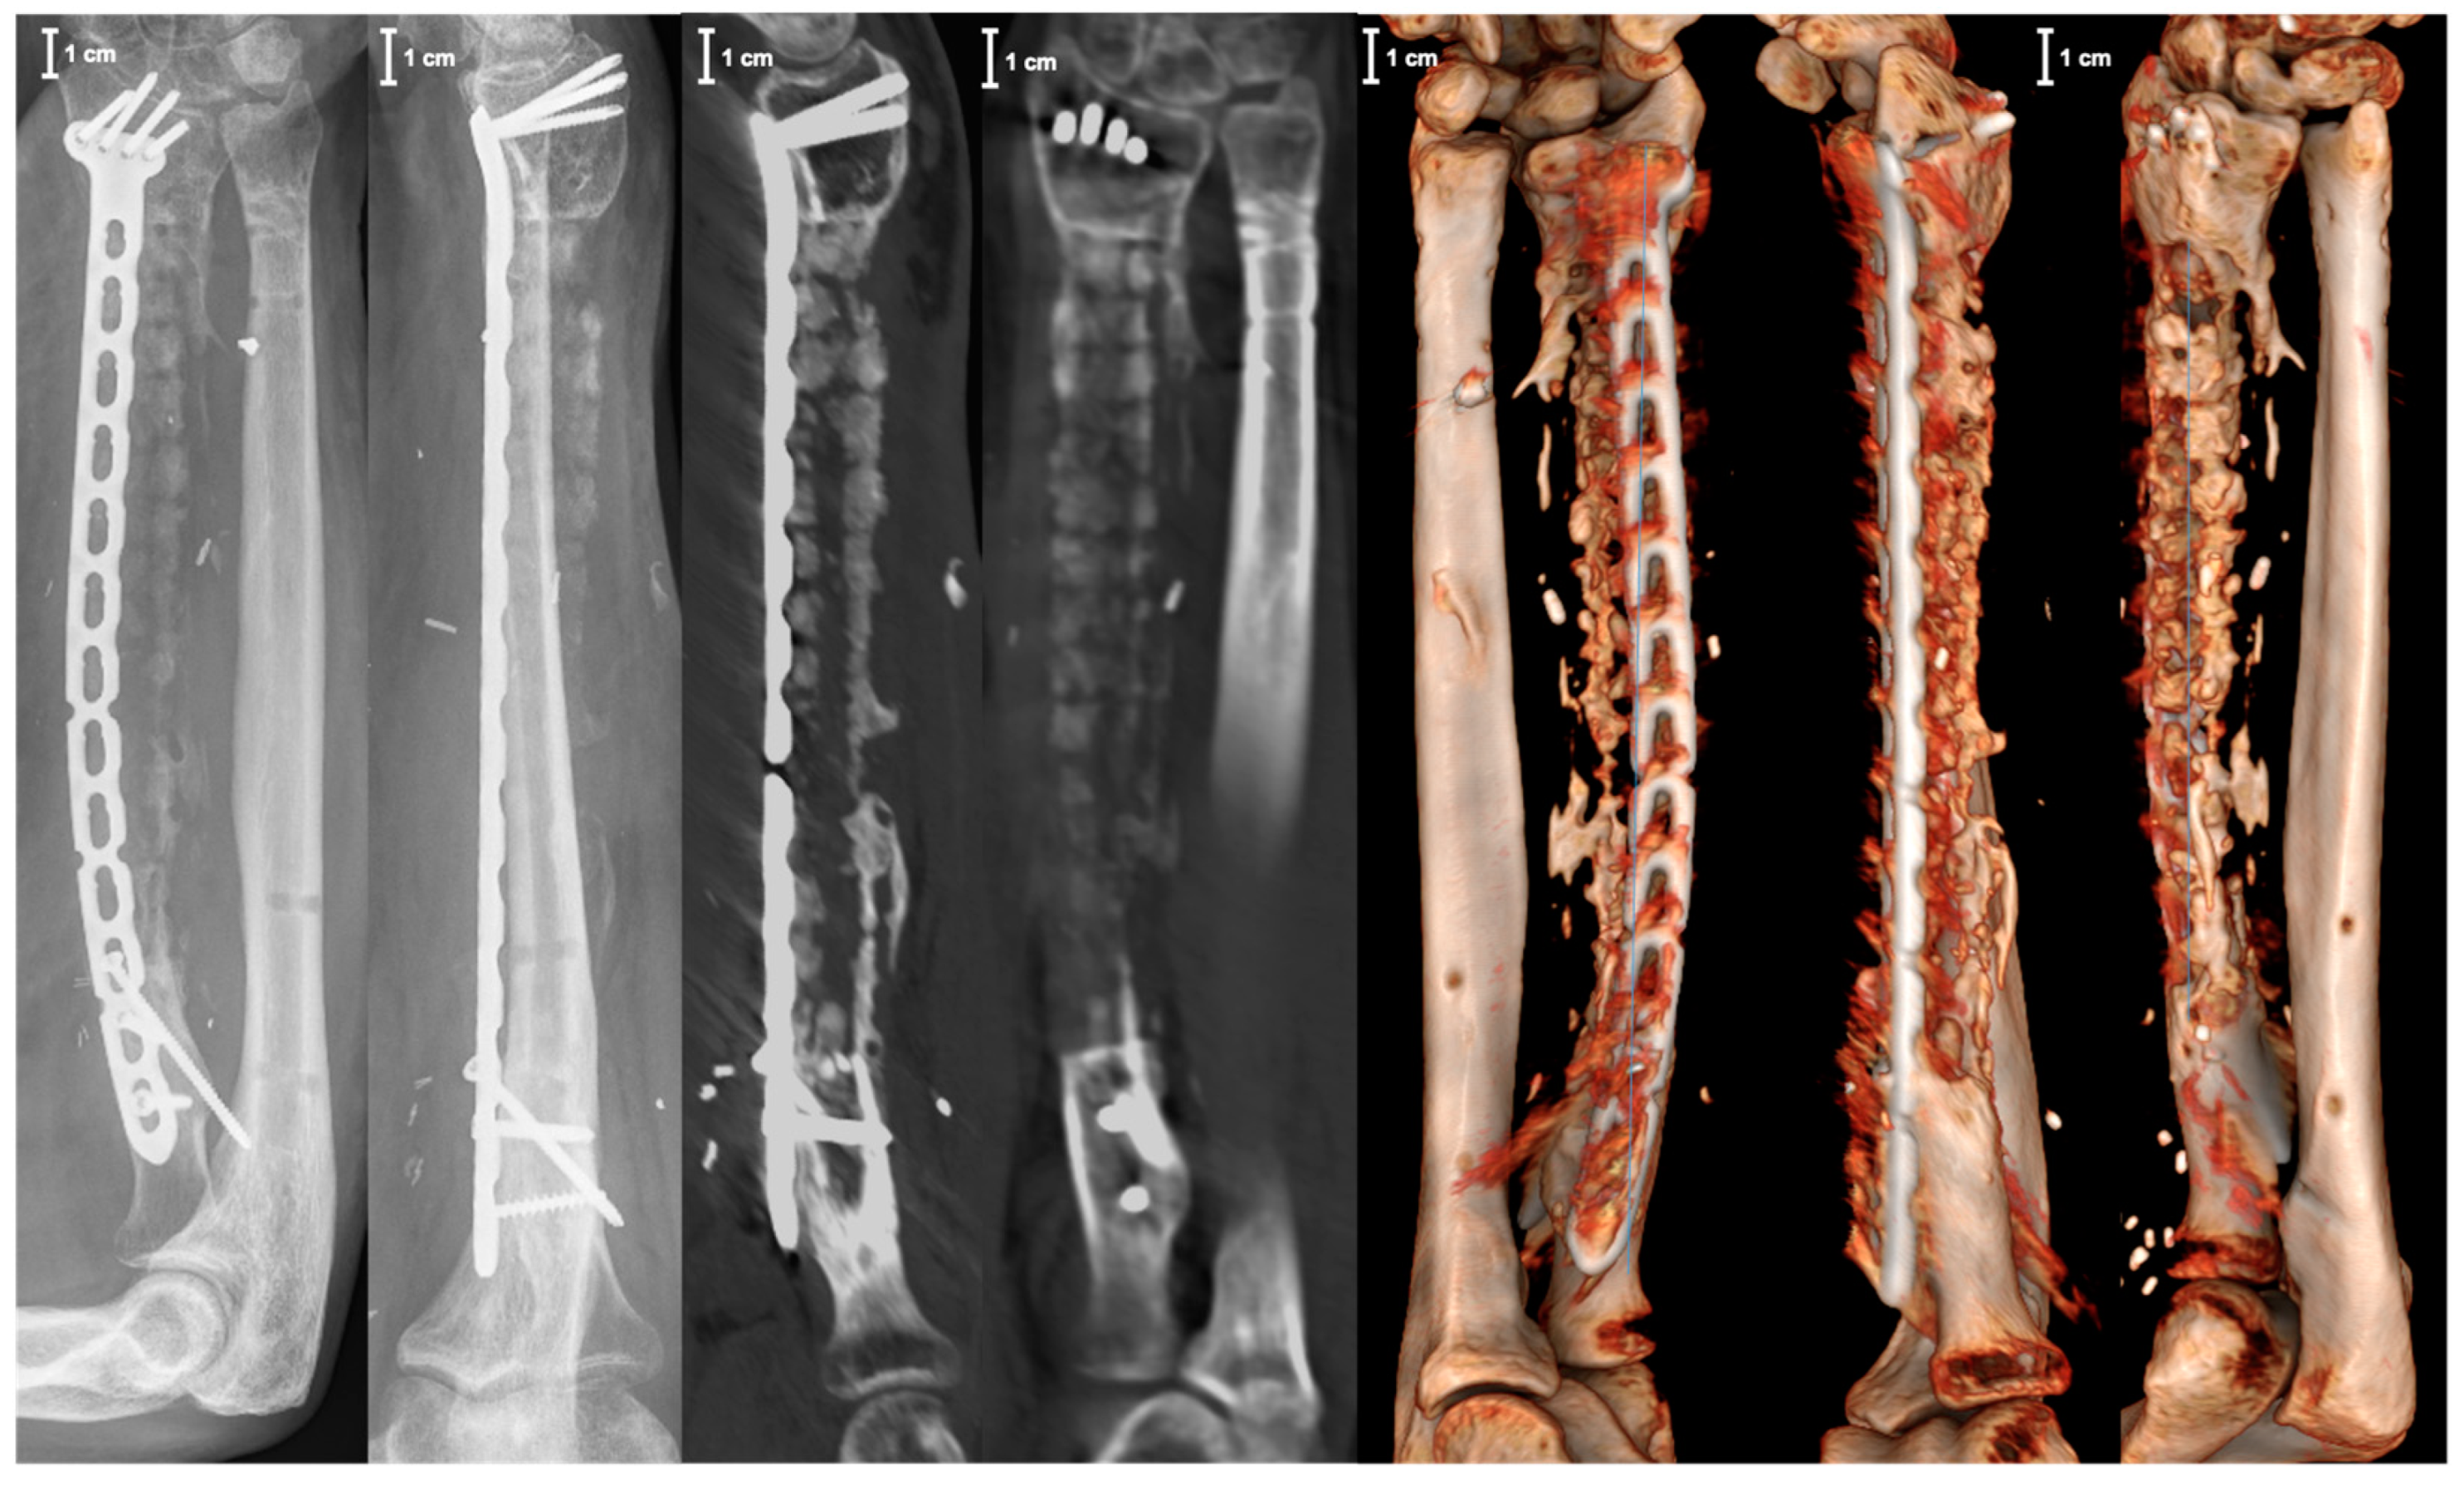

2. Case Report